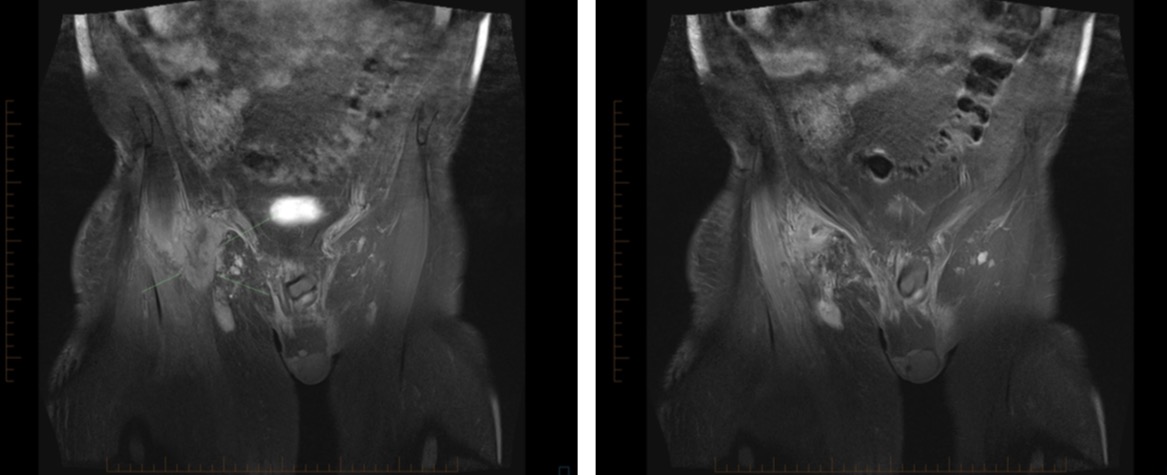

70 male prostate CA with groin mass

FEMORAL ARTERY LEIOMYOSARCOMA WITH BONE METASTASES.

• MORE OFTEN VENOUS THAN ARTERIAL (80%)

• MOST COMMON SITE IS IVC

• MOST COMMON ARTERY IS PULMONARY ARTERY

• METASTASES AT PRESENTATION ARE COMMON - APPROX 50%

• 5 YEAR RECURRENCE FREE SURVIVAL RATE APPROX 35% IN ONE SERIES